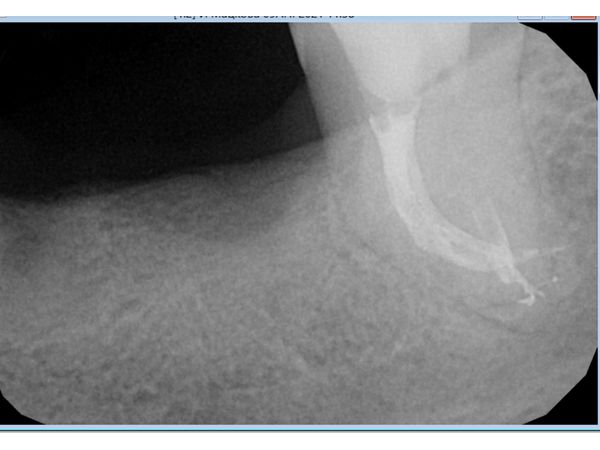

Исследование показало следы пломбировочного материала в медиальном (щёчном) корне зуба и запломбированный на две трети дистальный канал.

По данным снимка, оснований для отказа от повторного лечения не было, несмотря на аномальный изгиб медиального корня.

После проведённого лечения боль исчезла. Рентгенограмма показала, что женщина может рассчитывать на успешное протезирование.